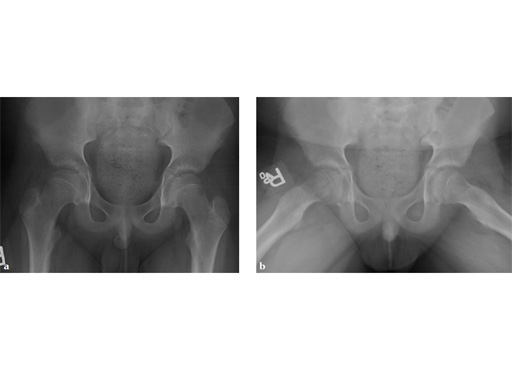

A boy aged 11 years and 3 months presented with a limp and had had pain in the thigh for 8 weeks.

Case provided by Richard Reynolds, Detroit, USA